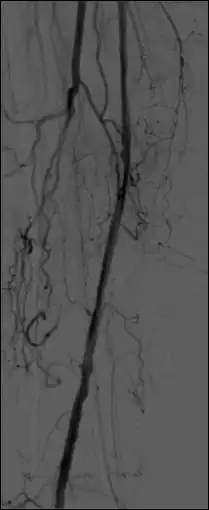

Use the Thick Slab module, in the MinIP mode to (effectively) integrate a number of live images so as to generate a vascular trace.

Pixel values displayed for subtracted images refer (correctly) to subtracted images with this option, although pixel shifting is not available. The Thick Slab module can be used to (effectively) integrate both mask images (before subtraction) and live images (before and following subtraction) so as to improve image SNR and to generate a vascular trace.